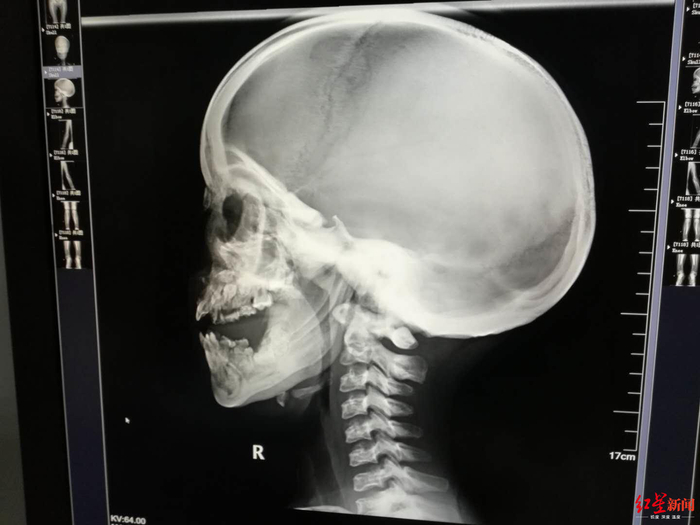

↑小女孩最终被确诊为患有石骨症

↑小女孩最终被确诊为患有石骨症,患者牙龈发育欠佳,牙例排列紊乱。受访者供图

↑小女孩最终被确诊为患有石骨症,患者接受了DR检查。受访者供图

此时已经是7月1日,玄玄住进耳鼻咽喉头颈外科20多天,徐幼马上给玄玄安排了全身DR骨扫描检查,第二天出结果,徐幼第一时间到放射科看片子,结果让她大吃一惊,又反复去看了多次,脑海里蹦出一个词:石骨症。

原来,从片子上看,玄玄从头骨到四肢、到脊椎,全身的骨头都发生的变化,骨质密度增高,骨髓腔闭塞,“正常人,骨髓腔里都是红色的骨髓,有造血的功能,但她的骨头,已经石化改变。”徐幼说,简单地理解,玄玄的骨头,从中空的变成了实心的,像大理石一样。